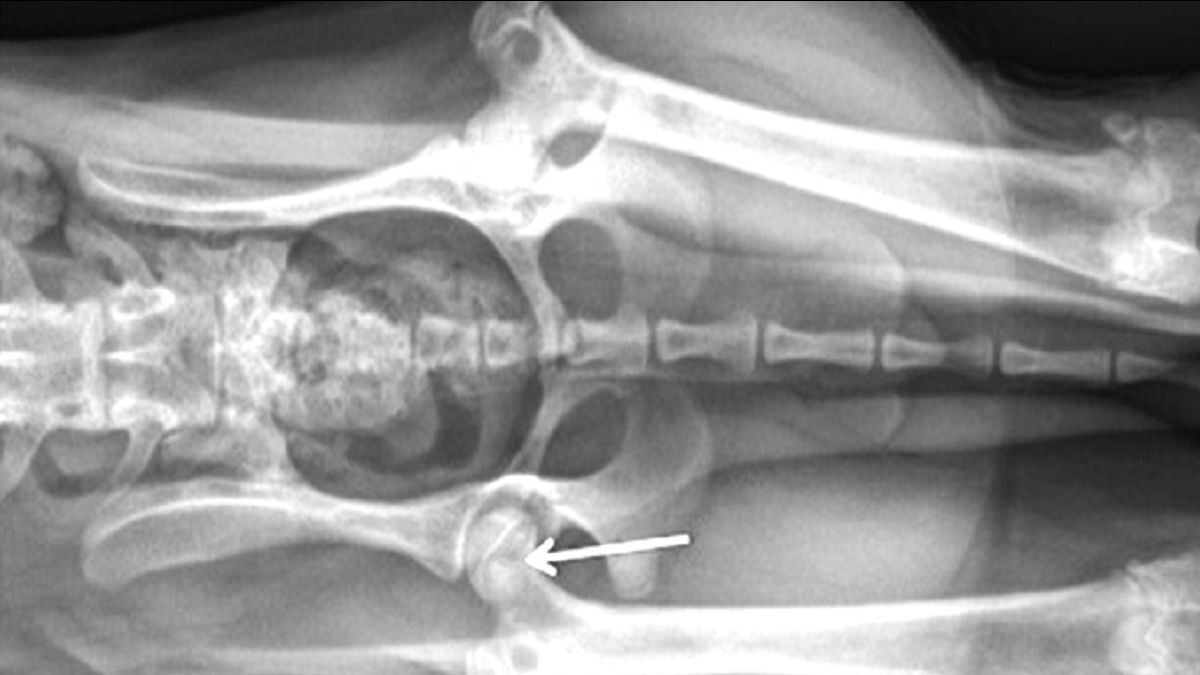

Tierneurologen Elektroenzephalographie EEG (FraW)